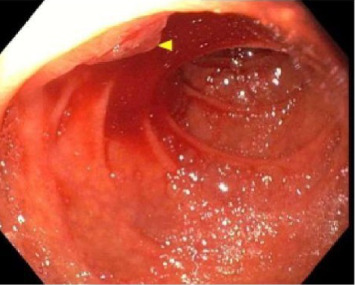

我们提出的情况下,49岁的男子入院急性肝功能衰竭合并血流动力学不稳定的胆道继发出血静脉曲张在胆管。由于静脉出血,放置全覆盖自膨胀裸金属支架(fcems)被认为是该患者肝动脉栓塞的最佳治疗选择。该手术的成功表明,fcems可以被认为是急性肝衰竭并发门静脉高压性胆道病并发血流动力学不稳定胆道患者肝移植的桥梁。

We present the case of a 49-year-old man admitted for acute liver failure complicated by hemodynamically unstable hemobilia secondary to bleeding varices in the bile duct. Placement of a fully covered self-expanding bare metal stent (FCSEMS) was considered the best treatment of choice over hepatic artery embolization in this patient because of the venous source of bleeding. The success of this procedure indicates that FCSEMS can be considered as a bridge to liver transplantation in patients with acute liver failure who develop hemodynamically unstable hemobilia secondary to portal hypertensive biliopathy.